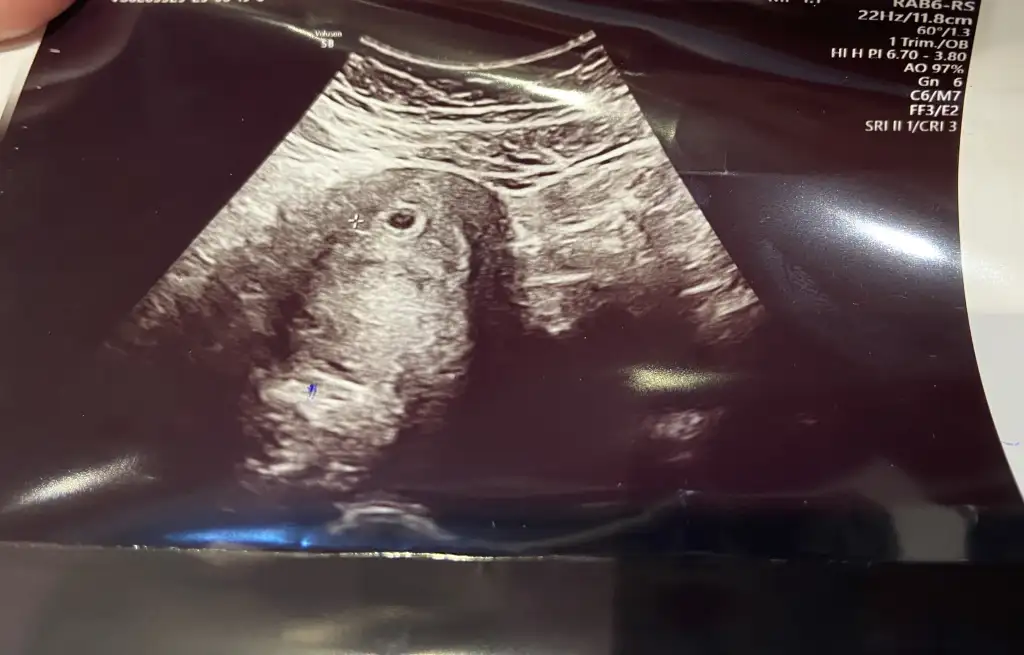

Ya kafam şeye takıldı. Bugün kese boyu 4 mm on gün sonra 14 mm olur kalp atışı da 18 19 mm den sonra duyuluyor deniliyor o zaman ben on gün sonra duyamayacak mıyım korkuyorum şu an 😞😞 senin kese gördüğün kese boyutu ve kalp atışı duyduğunda kaçtı acaba

Kız böyle hesaplamalar yapma 😁😁 ben de 6+4’te görmüştüm ilk kalp atışını. Hangi kese kaç mm filan öyle şeyleri düşünme bak çok şükür yolk sac gözüktü 😍 senin dikkat etmen gereken tek şey beslenmen artık ♥️ multivitamin alıyosan devam et 👍🏻

Tamam tamam bence de düşünmeyeyim yoksa kafayı yicem 😅 evet alıyorum folidays 🥰 güzel güzel beslenip günümü bekleyeceğim 🥰🥰

Ama yolk saç göründüyse kalp atışı olur artık dimiii 🥹

Kızlar ben bugün devlet hastanesine gittim gebelik rutini tahlillerimi yaptırmak için oraya gitmişken doktor tekrar ultrason ile baktı bu sefer de kese 9 mm çıktı 😊 yani anladım ki ultrasondan ultrasona çok değişiyor kese boyunu bilmek gerçekten de çok önemli değil 😅 fufucum fufucum

Kız evet boşuna mı diyoruz takılma ona sen hiiiçç 😂😂 her gittiğin farklı doktor cihaz değişiyo. Doktorun ölçümlemesine göre bile değişir o. 😂😂